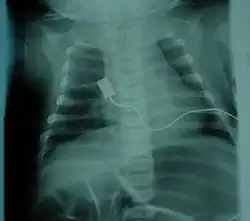

X-ray showing bell-shaped torso due to atrophy of intercostal muscles and using abdominal muscles to breathe. Bell-shaped torso is not specific to individuals with SMA.

• Bell-shaped torso (caused by using only abdominal muscles for respiration) in severe SMA type